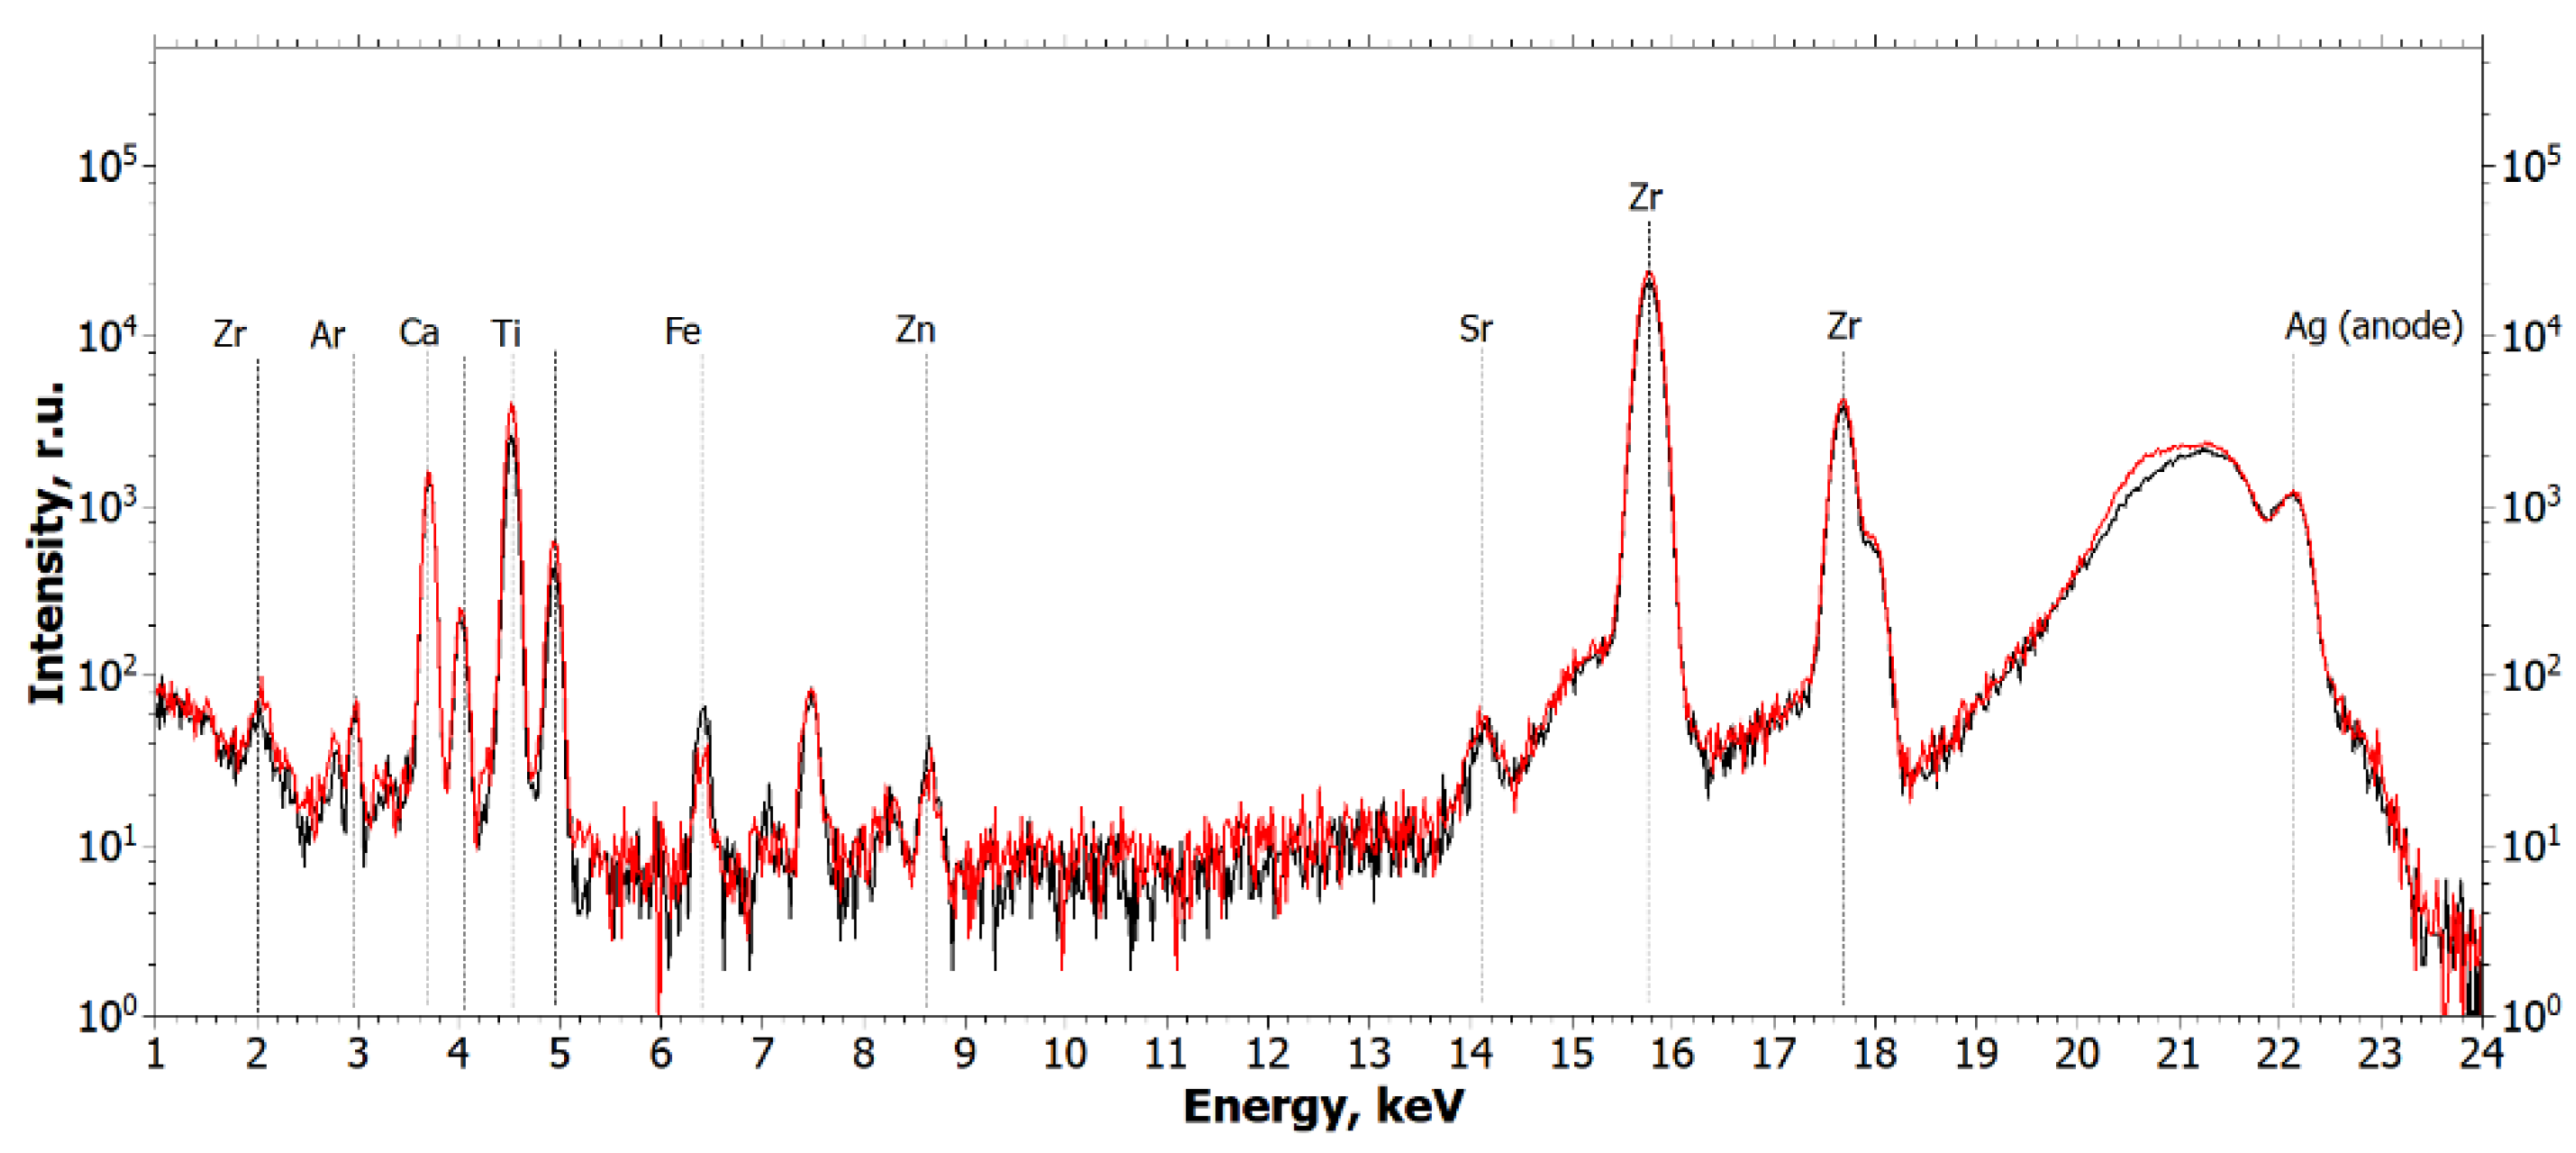

2.1.1. Results of X-ray and Electron Microscopic Studies

4.3. X-ray Fluorescence Analysis (XRF)

- Ag tube (focus size 10 × 1.0 mm), 40 kV × 40 mA mode;

- Monochromator—silicon (symmetrical), reflection (111);

- Wavelength—0.55 Å (E = 22.162 keV);

- Beam size—10.0 × 1.0 mm (slits adjustable);

- Detector—Amptek 123SDD (Amptek, Bedford, MA, USA);

- Exposure—1200 s per measurement.